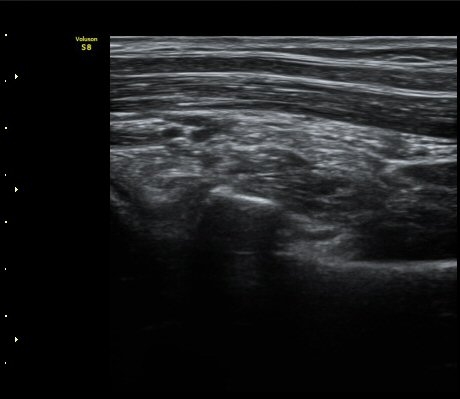

ÆÈ²ÞÄ¡ ¿ÜÃø¿¡¼­ ½ÃÇàÇÑ ¿ä°ñµÎ Á¾´Ü¸é°Ë»ç¿¡¼­ ¿ä°ñµÎ¿Í ¿ä°ñ °æ°èºÎ°¡ ¿¹°¢À¸·Î ÀÌÇàµÇ°í

°æ°èºÎ¿¡ ¼Ò·®ÀÇ ¼ö¾×Àú·ù°¡ °üÂûµÊ(±×¸² 2)